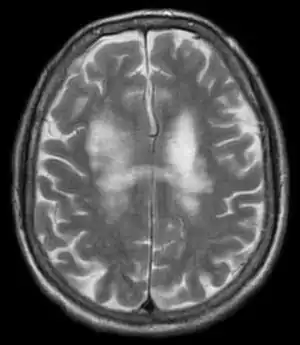

PML is diagnosed in a patient with a progressive course of the disease, finding JC virus DNA in spinal fluid together with consistent white-matter lesions on brain magnetic resonance imaging (MRI); alternatively, a brain biopsy is diagnostic[1] when the typical histopathology of demyelination, bizarre astrocytes, and enlarged oligodendroglial nuclei are present, coupled with techniques showing the presence of JC virus.[12]

Characteristic evidence of PML on brain CT scan images are multifocal, noncontrast enhancing hypodense lesions without mass effect, but MRI is far more sensitive than CT.[12] The most common area of involvement is the cortical white matter of frontal and parieto occipital lobes, but lesions may occur anywhere in the brain, such as the basal ganglia, external capsule, and posterior cranial fossa structures such as the brain stem and cerebellum.[12] Although typically multifocal, natalizumab-associated PML is often monofocal, predominantly in the frontal lobe.[12]